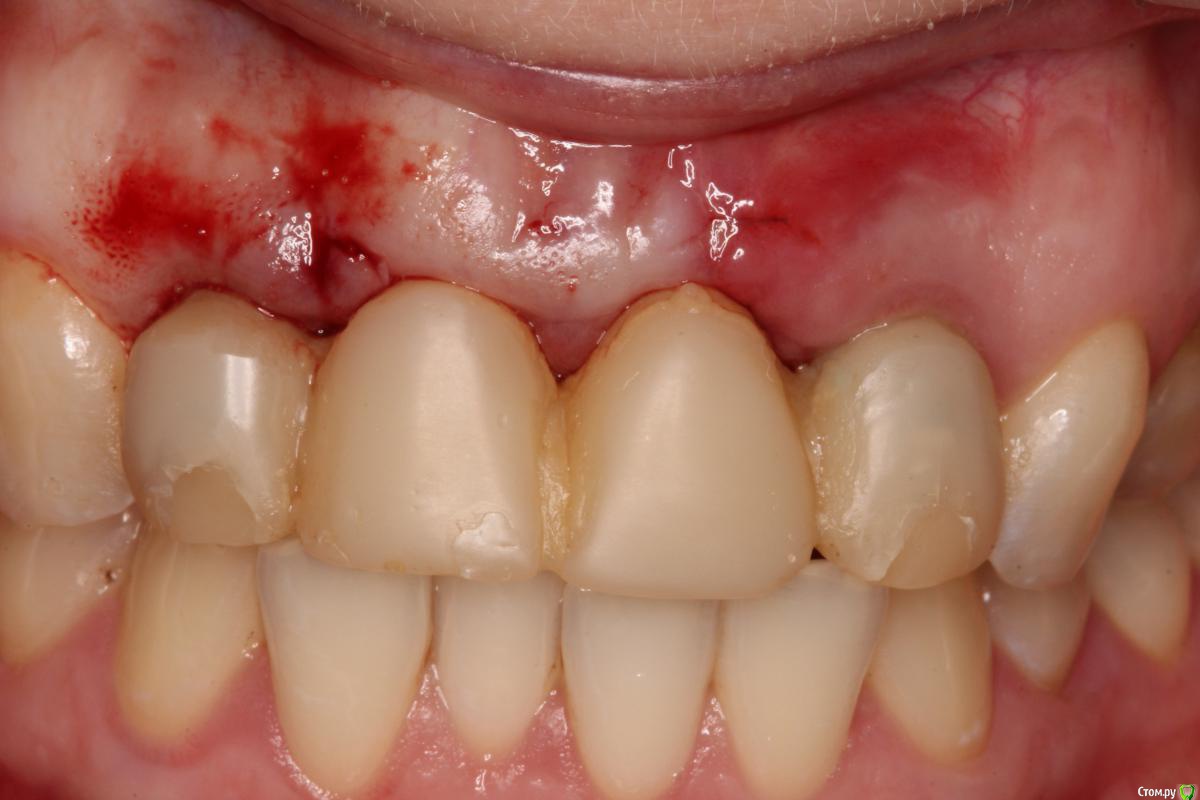

Популярный пост Ст@ся Опубликовано 20 августа, 2016 Автор Популярный пост Поделиться Опубликовано 20 августа, 2016 28 Ссылка на комментарий

diesel87 Опубликовано 20 августа, 2016 Поделиться Опубликовано 20 августа, 2016 Ещё будете подсаживать или ждать? Ссылка на комментарий

Ст@ся Опубликовано 21 августа, 2016 Автор Поделиться Опубликовано 21 августа, 2016 Ещё будете подсаживать или ждать?Пациентку результат устроил. 1 Ссылка на комментарий